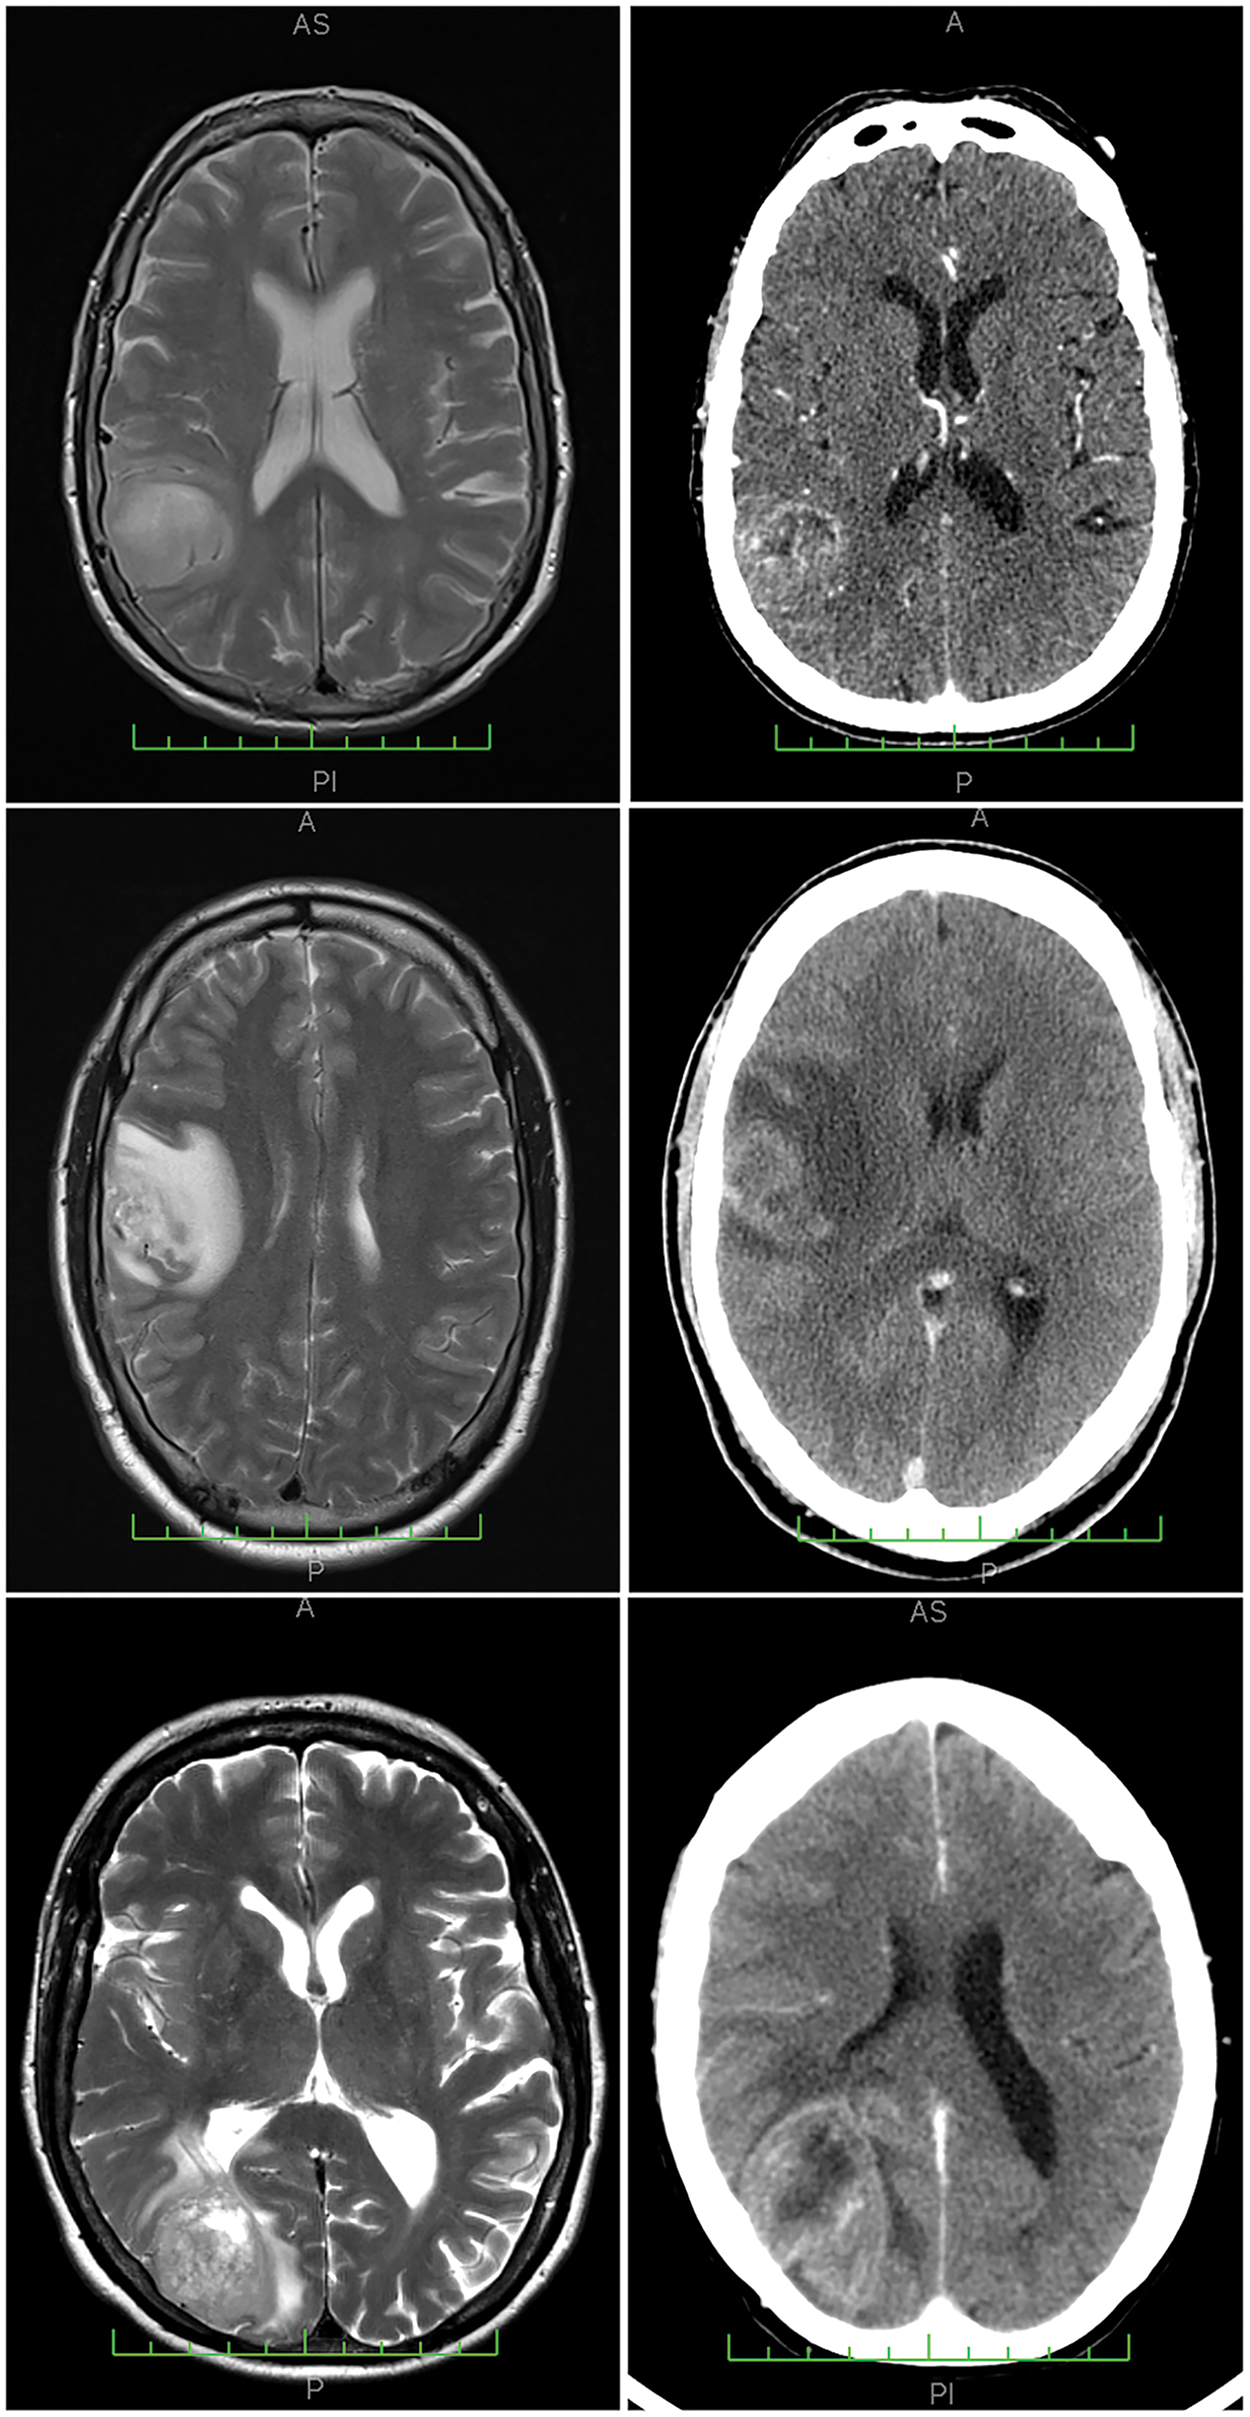

This research involves the analysis of two distinct cohorts of human glioblastoma cases (Cohort 1 and Cohort 2, see Tables A1, A2). Cohort 1 of 34 WHO Grade 4 glioma samples used in this study was provided by the Australian Genomics and Clinical Outcomes of Glioma (AGOG) tissue bank (University of Sydney Human Ethics Committee Project number 2016/027). A second independent cohort of 25 cases was provided by the Sydney Brain Tumor Bank (Royal Prince Alfred Hospital Ethics Committee Project number 2019/ETH07282) and used for validation purposes. Paraffin sections were stained with H&E (Hematoxylin and Eosin) and scanned using an Olympus VS-120 scanner (VS120 Virtual Slide System, Olympus, Japan). The Department of Neuropathology at Royal Prince Alfred Hospital processed adjacent sections for immunohistochemistry. The well-established microglia and macrophage markers IBA1 and CD163 were processed according to manufacturers’ recommendations. Anti-CD163, clone 10D6 (Leica, Australia, cat no. CD163-L-CE), was used following antigen retrieval at 90°C for 30 min. Incubation was carried out at 1:200 for 60 min. Anti-IBA1 (Wako, Japan, cat no. 019-19741) was incubated at 1:1000 for 60 min following antigen retrieval. Whole-slide scans of the immunolabeled paraffin sections were obtained at 40× magnification. All cases had been originally diagnosed according to the fourth edition of the WHO classification for CNS tumors which was updated in 2021. This required the reclassification of some cases which were excluded. Thirty-three glioblastoma cases remained in the first cohort. Thus, there were no consequences for the conclusions of this study. The neuroimaging of cases was also reviewed (Fig. 1, Tables A1, A2). Survival statistics were obtained by applying a Kaplan Meier and Cox Proportional Hazards model. QuPath [16] was used for viewing WSIs.

Figure 1: Neuroimaging results from three representative cases analyzed, with corresponding MRI (magnetic resonance imaging) scans on the left and CT (computerized tomography) scans on the right. The cases presented are: Case 25 (top row), Case 6 (center row), and Case 1 (bottom row), all from Cohort 1. Example histological findings for these cases can be found in Fig. 3.